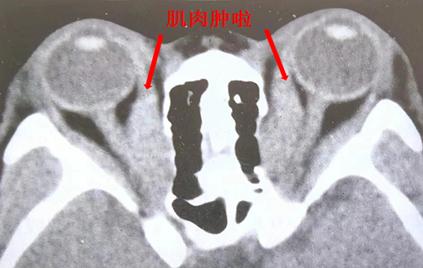

眼外肌受累时导致眼球运动障碍,检查可显示眼外肌肥厚、眼球突出,随着病情加重,复视也会加重。

图源:作者提供角膜病变